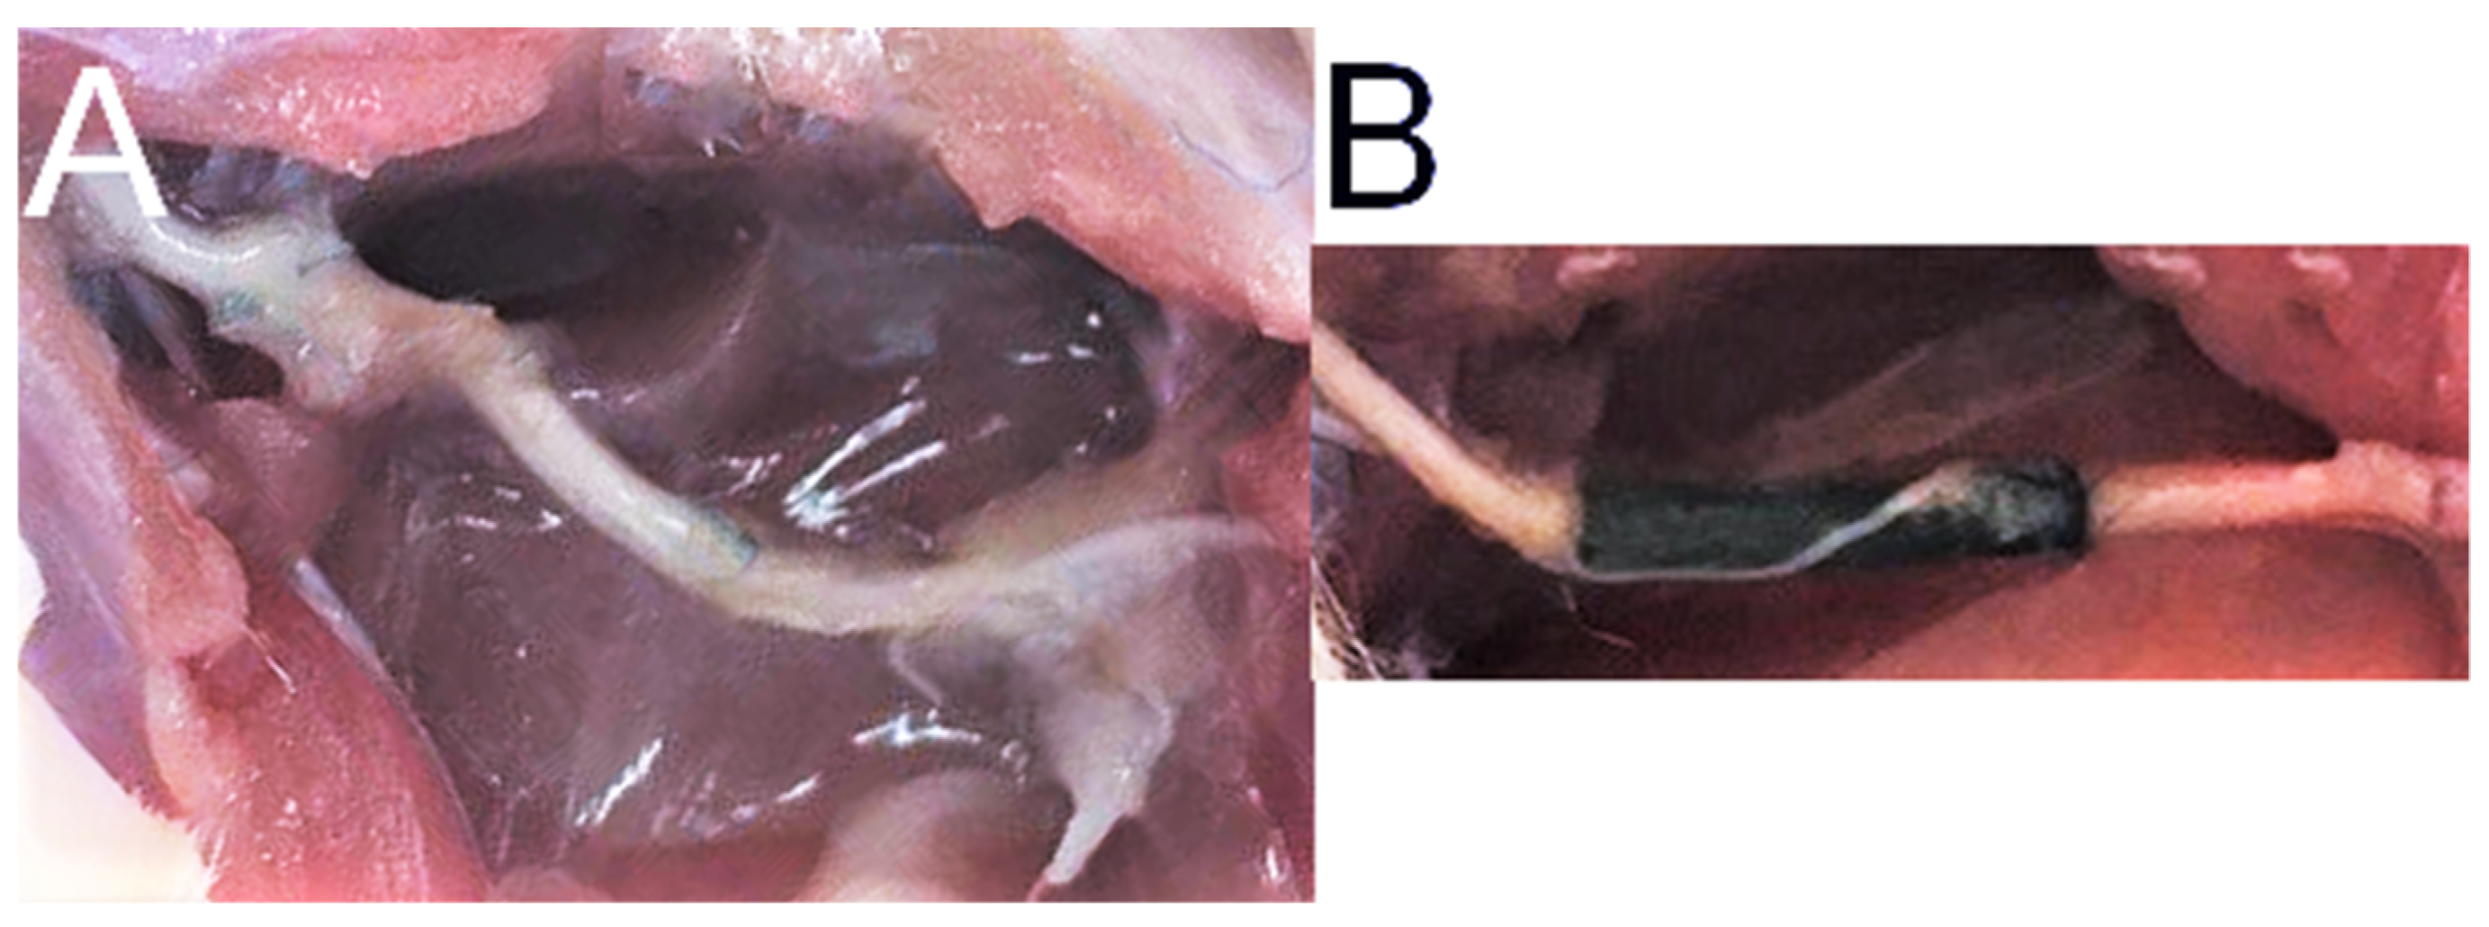

2.3. Animal Study and SFI